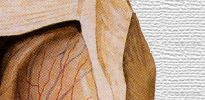

Cuerpo

calloso |

Lámina

del septum pellucidum |

Cavidad

del septum pelllucidum |

Columna

del fórnix |

Núcleo

caudado |

Glándula

pineal |

Tercer

ventrículo |

Gran

vena cerebral |

Ovillo

coroideo |

Cerebelo |

Plexo

coroideo del ventrículo lateral |

vv.

cerebrales internas |

v.

tálamoestriada superior |

coroidea superior |